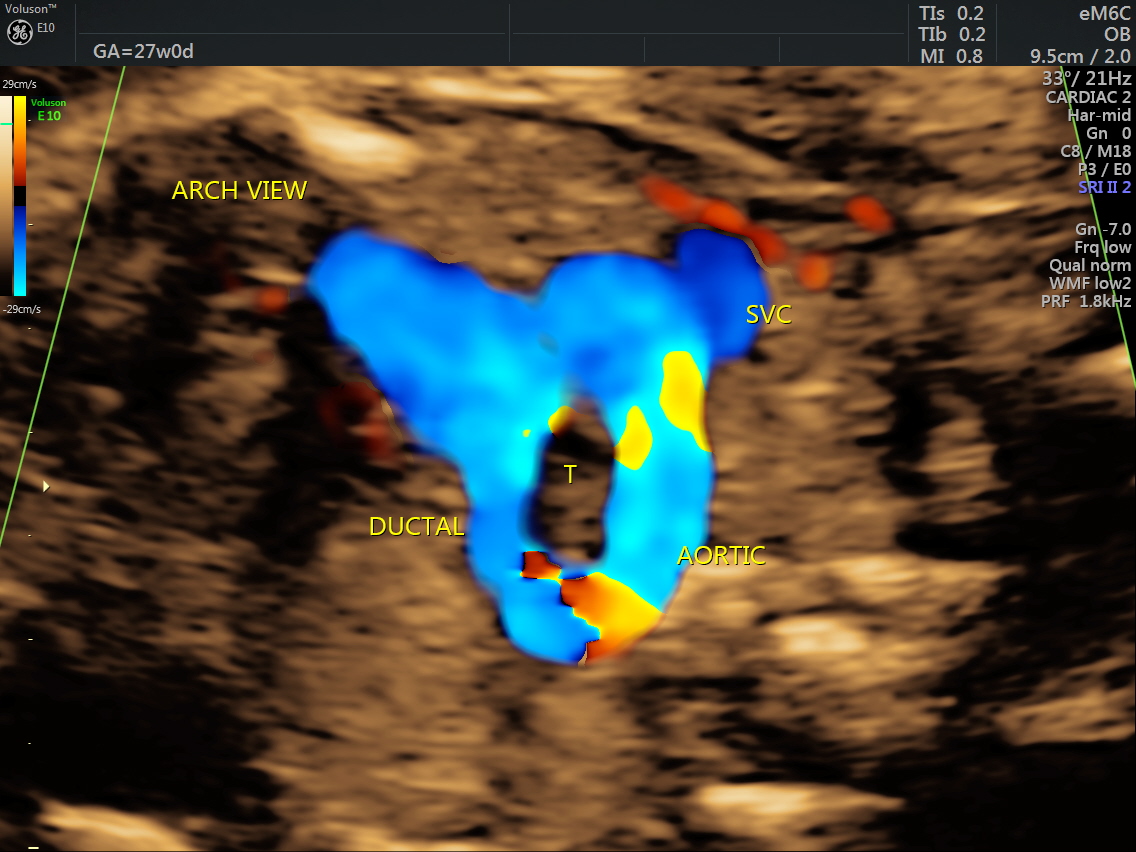

RT AORTIC ARCH_32 Published June 17, 2016 at 1136 × 852 in Rt aortic arch and aberrant left subclavian artery ← Previous Next →